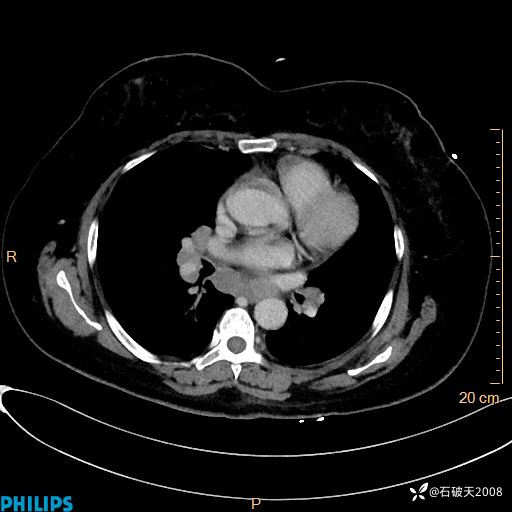

肺结节病?纵膈型肺癌?淋巴瘤?有点意思,欢迎围观

女 52岁 主 诉:咳嗽10余天,咳痰2天。

现病史:10余天前无明显诱因出现咳嗽,呈阵发性干咳,伴咽喉部发痒,无咽痛,无咳痰,无鼻塞、流涕、打喷嚏,无发热、畏寒、寒颤,无头痛、头晕,无胸闷、胸痛,无反酸、烧心,无腹痛、腹泻,无尿频、尿急,无皮疹等,在当地诊所求治,给予口服药物治疗(具体不详),病情无好转。遂在当地社区卫生服务中心开具口服药物治疗(具体不详),疗效欠佳。2天前出现咳痰,在我院门诊求治,行胸部CT提示肺部感染,建议住院,患者要求口服药物治疗,目前仍咳嗽、咳白色粘痰,白天量多,夜间自觉喉部喘鸣音,遂再次来院就诊,以“肺部感染”为诊断收入院。发病以来,神志清,精神可,饮食可,夜间睡眠差,大小便正常,近期体重无明显变化。

纵隔窗